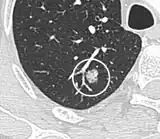

- In case of subsolid nodules, being part solid has a higher risk of cancer than being purely ground glass opacity.

-

Part solid nodule.[9] -

Ground glass opacity nodule.[9]